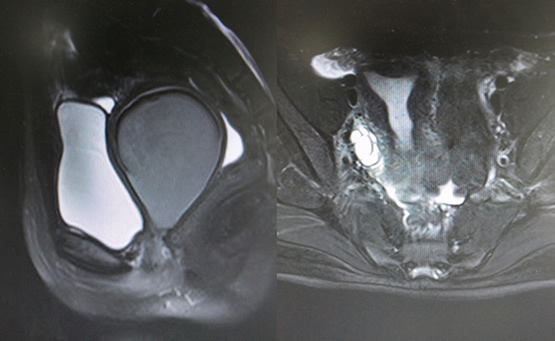

2石女是什么样子图片

石女的图片

石女是什么样子图片

石女照片石女图